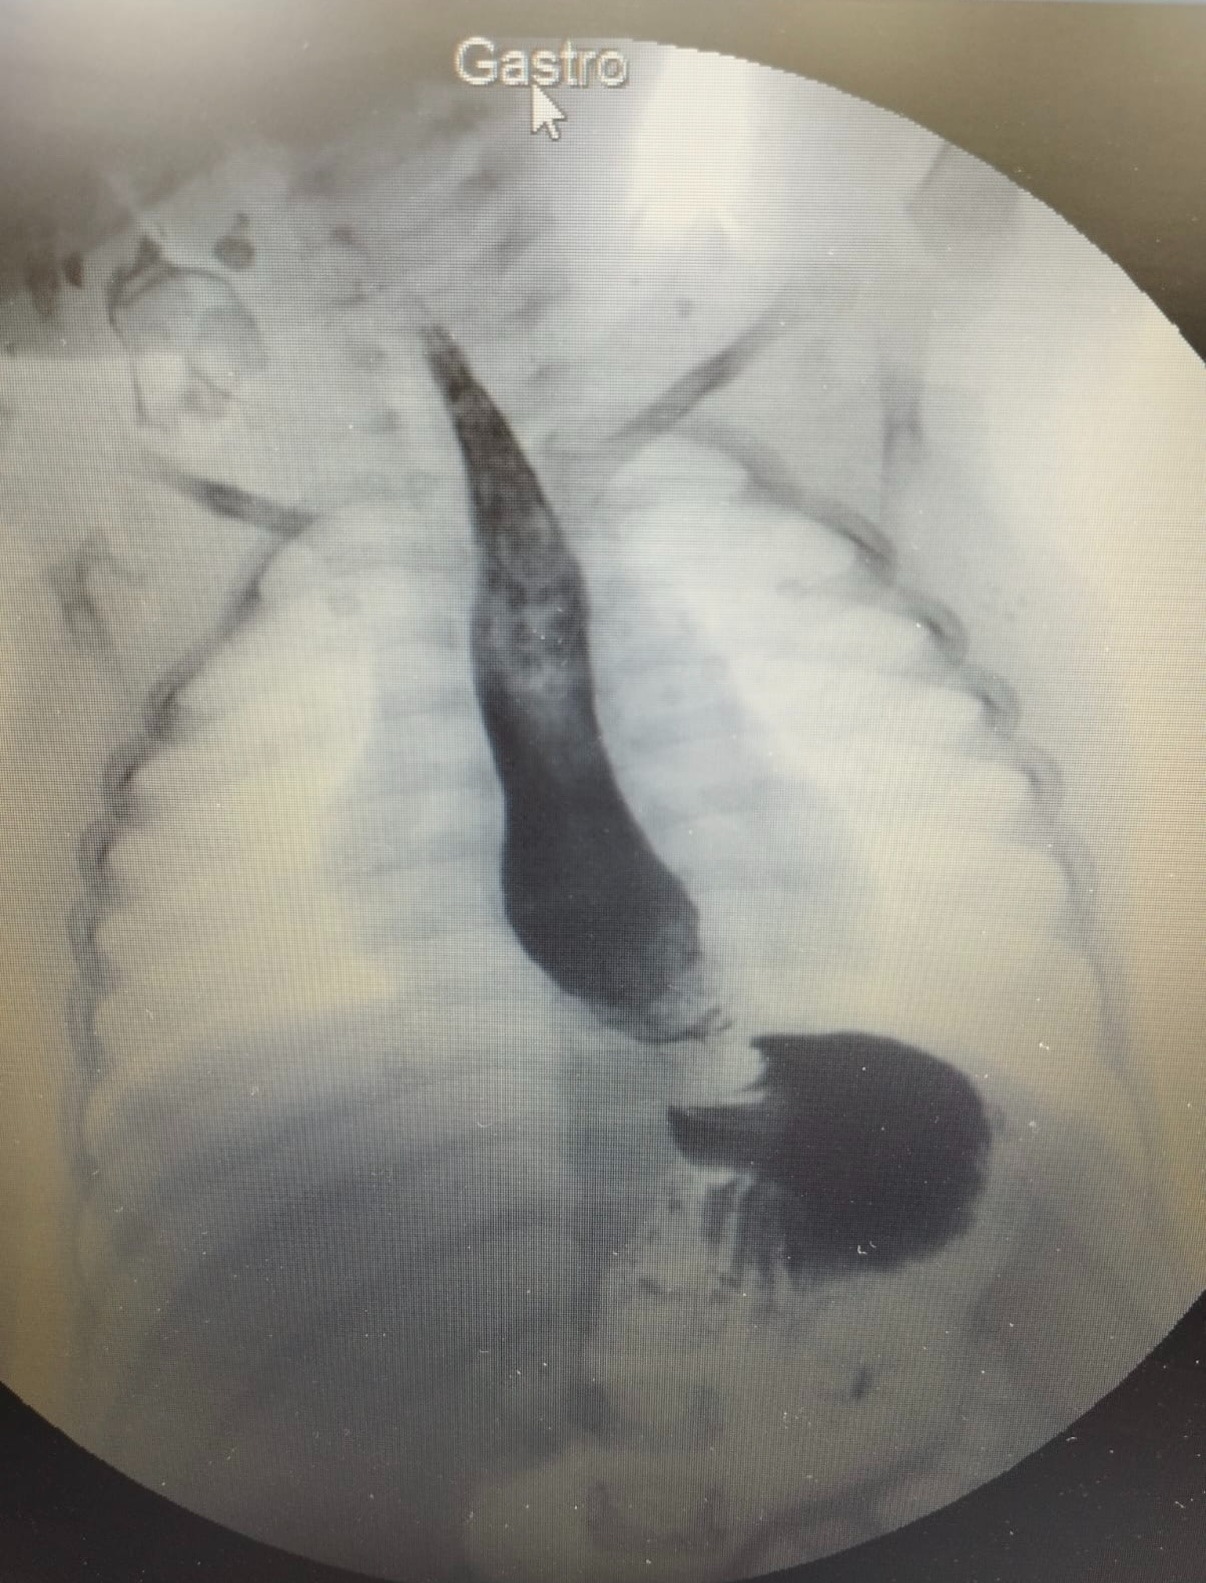

My name is Lena and I am trying to raise funds for Kenan, a 4 year old child from Gaza who has a hiatal hernia which could be fatal if left untreated. He urgently needs an operation.

They need 4300€ for Kenan's oesophageal surgery, and an additional 1700€ for food and hygiene products during recovery period.